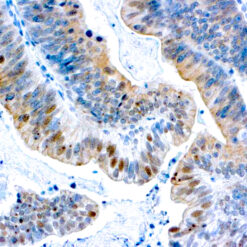

This antibody recognizes insoluble elastin, α-elastin, soluble non-cross linked precursor of elastin (tropoelastin). Elastin is an important polymeric protein of connective tissue that imparts elasticity to vertebrate elastic tissues.

| Cellular Localization | Connective tissue |

| Positive Control Tissue | Heart, Kidney |